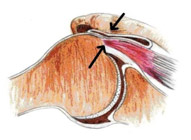

I tendini della cuffia dei rotatori scorrono in uno spazio (spazio subacromiale) costituito superiormente dalla porzione della scapola chiamata acromion e inferiormente dalla testa dell’omero. Una borsa sierosa si interpone tra ossa e tendini per facilitare il loro scorrimento.

- sindrome da conflitto. Lo spazio sottoacromiale può ridursi per svariati motivi causando l’irritazione dei tendini durante il loro scorrimento e provocandone l’infiammazione. L’elevazione della mano e del braccio sopra la spalla riduce fisiologicamente questo spazio e può causare dolori anche in una spalla normale.

Lo scopo della chirurgia è quello di aumentare lo spazio sottoacromiale per decomprimere i tendini della cuffia. La cosiddetta acromionplastica prevede sia la rimozione della borsa infiammata (bursectomia), sia l’asportazione parziale dell’acromion. Queste procedure possono essere eseguite usando una tecnica artroscopica o aperta. Le tecniche artroscopiche permettono di trattare gran parte delle patologie della cuffia dei rotatori con una invasività limitata e un recupero funzionale più veloce.

In caso di rottura della cuffia, alla suddetta pratica chirurgica può affiancarsi anche la sutura tendinea. Le tecniche di sutura dei tendini lesionati sono molteplici e hanno indicazioni diverse a seconda della tipologia della lesione.